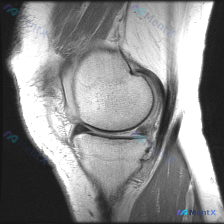

刚看到一张有意思的膝关节MRI读片病例,整理出来分享下思路。 病例影像资料 提供的是膝关节MRI-T1加权序列冠状位图像,分析可见: 1. 骨骼结构:股骨远端、胫骨近端皮质连续,无明显骨折或骨质破坏;T1序列骨髓信号为弥漫中等信号,无明显异常低/高信号 2. 半月板:内、外侧半月板形态信号均正常,内...

刚整理了一份很有借鉴意义的膝关节MRI读片病例,初诊怀疑软骨异常,最终系统读片发现了更明确的病变,分享一下完整分析思路。 病例影像基本信息 这是一份膝关节矢状位质子密度加权(PDWI)MRI影像,图像清晰度良好,解剖结构辨识度高,无明显运动伪影,满足诊断要求。PDWI序列对半月板和软骨结构的观察敏感...